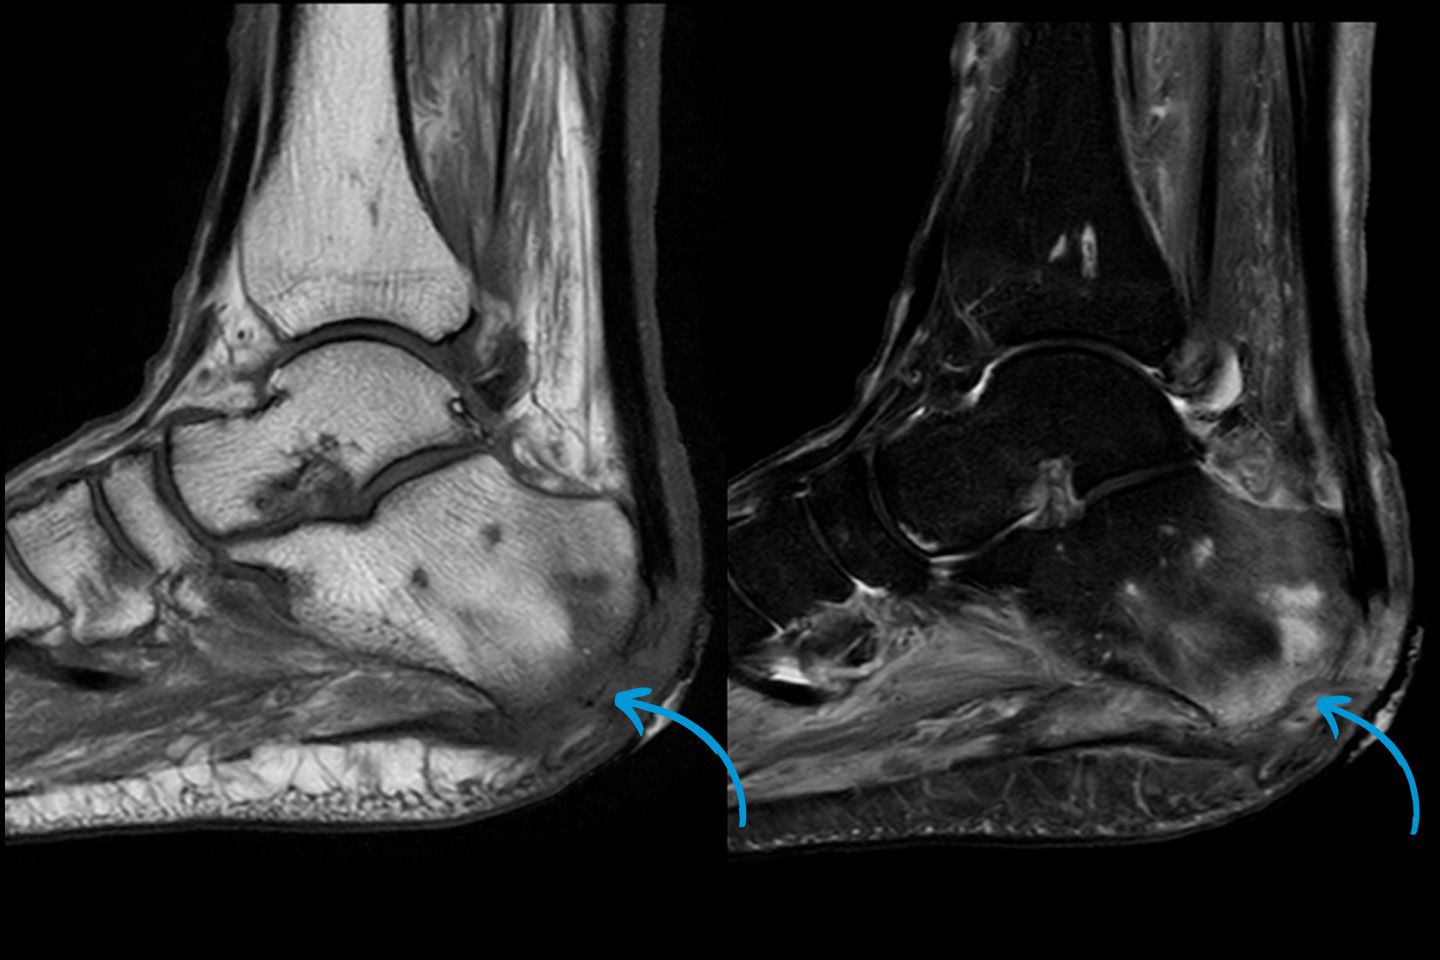

Osteomyleitis (Infektion des Knochenmarks) am Fuss.

Durch den Einsatz moderner Verfahren wie Ultraschall, Röntgen, Magnetresonanztomographie (MRT) und Computertomographie (CT) können wir präzise Bilder des Bewegungsapparates erstellen. Diese ermöglichen es, die Ursachen von Beschwerden zu erkennen und gezielte Behandlungen einzuleiten. Dazu zählen Frakturen, Bänderverletzungen, Gelenkerkrankungen, degenerative Erkrankungen oder Tumorerkrankungen. Moderne Datenverarbeitung, wie die Integration von 3D-Bildgebung und hochauflösenden Techniken, gewährleistet präzise Diagnosen auf höchstem Niveau.